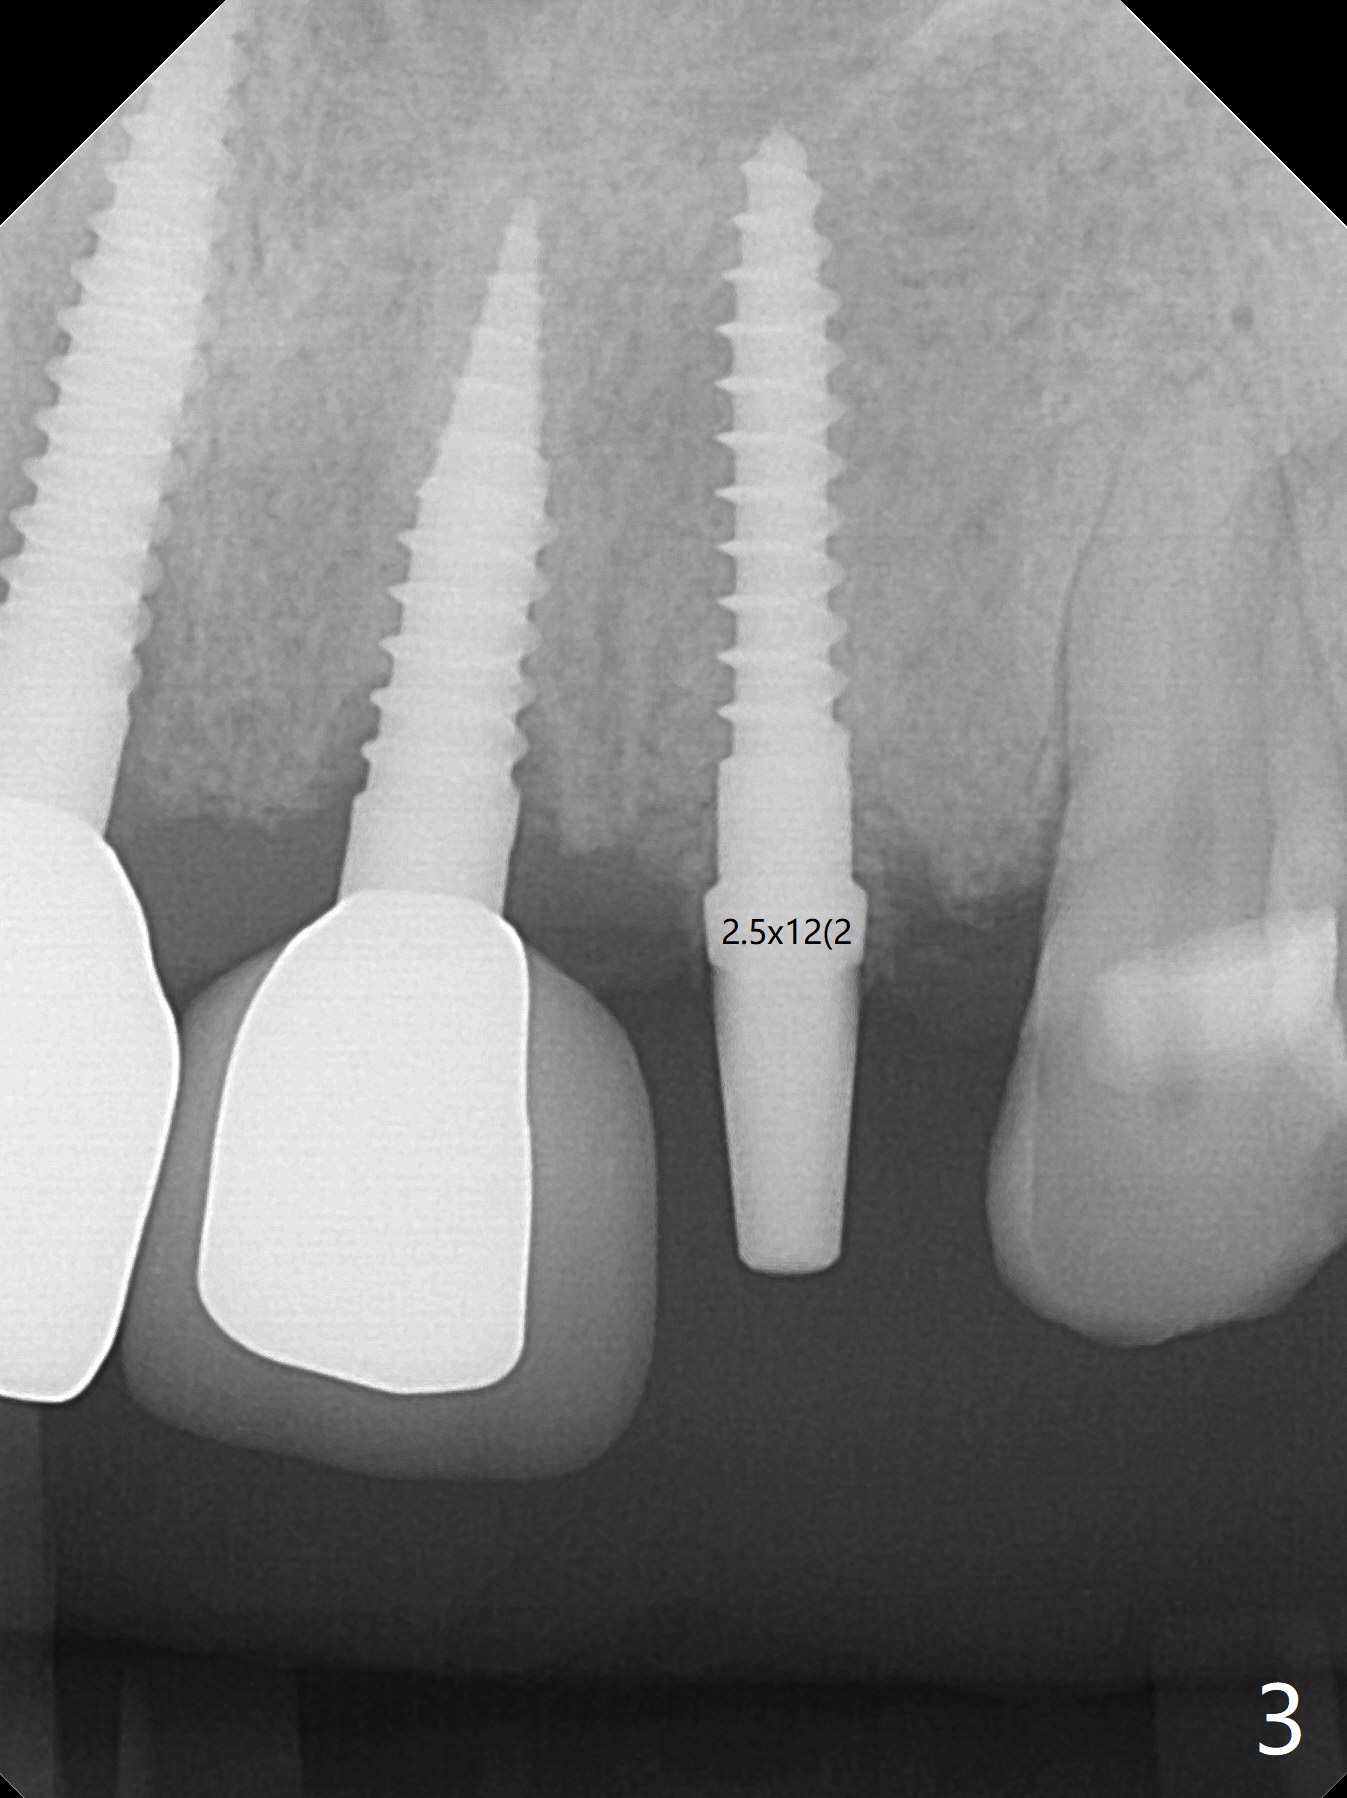

A 64-year-old man requests implant for the loose tooth at #10. The bone width is 5.5 mm (Fig.1); with 2.5 mm implant, there is 1.5 mm of the bone on the either side of the implant. The ideal width is 2 mm, which is safe, preventing buccal or palatal plate perforation. The buccal crest is lower when the tooth is extracted (Fig.4). Following trajectory confirmation (Fig.2), a 2.5x12(2) mm implant is placed a little deeper than expected to ensure no implant thread exposure with bone graft (Fig.3,5). The bone loss at #8 and 9 (Fig.2,3) is associated with the narrow ridge. The surface treatment of 1-piece implants is not as good as that of regular ones. The threads appears to be covered by the bone or bone graft 4 months postop (Fig.6).